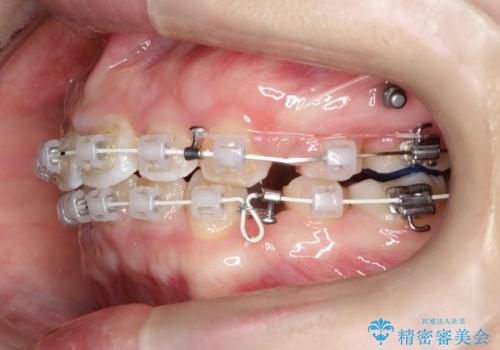

上下左右小臼歯を抜歯して審美装置で治療を行いました。

抜歯したスペースをきちんと下げることができるように、矯正用のアンカースクリューを用いて治療をしております。